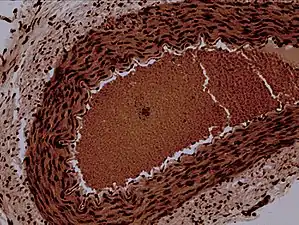

![]() Rabbit arteriole at 100X | |

Arterioles have muscular walls (usually only one to two layers of smooth muscle cells) and are the primary site of vascular resistance. The greatest change in blood pressure and velocity of blood flow occurs at the transition of arterioles to capillaries. This function is extremely important because it prevents the thin, one-layer capillaries from exploding upon pressure. The arterioles achieve this decrease in pressure, as they are the site with the highest resistance (a large contributor to total peripheral resistance) which translates to a large decrease in the pressure.[2]

Microanatomy

In a healthy vascular system the endothelium lines all blood-contacting surfaces, including arteries, arterioles, veins, venules, capillaries, and heart chambers. This healthy condition is promoted by the ample production of nitric oxide by the endothelium, which requires a biochemical reaction regulated by a complex balance of polyphenols, various nitric oxide synthase enzymes and L-arginine. In addition there is direct electrical and chemical communication via gap junctions between the endothelial cells and the vascular smooth muscle.